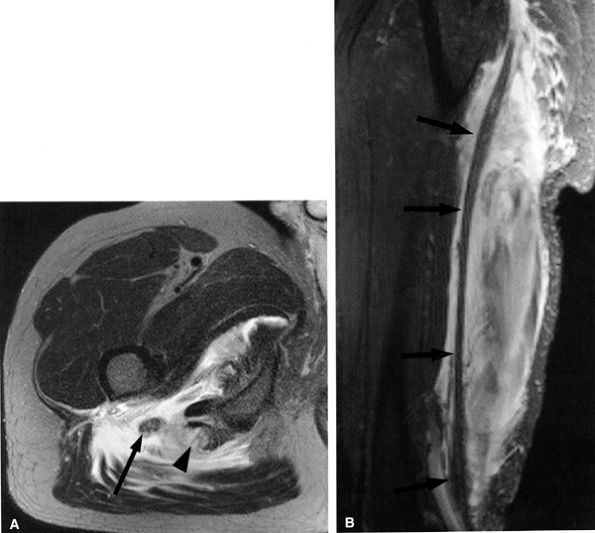

FIGURE 6.29 ● Common peroneal neuropathy secondary to a nerve sheath tumor. (A) Coronal T2-weighted fat-suppressed image demonstrating a nerve sheath tumor of the common peroneal nerve (arrow). (B) Sagittal T1-weighted image showing denervation atrophy of the anterior tibial muscle (arrows).

|

FIGURE 6.31 ● Surgically proven common peroneal neuropathy and denervation secondary to a hypertrophied biceps femoris muscle. (A) Axial T1-weighted image showing the common peroneal nerve (arrow) entrapped between a hypertrophied short head of the biceps femoris muscle (white asterisk) and the lateral head of the gastrocnemius muscle (black asterisk). (B) Axial T2-weighted fat-suppressed image displaying denervation edema in the anterolateral compartment muscles (arrows).